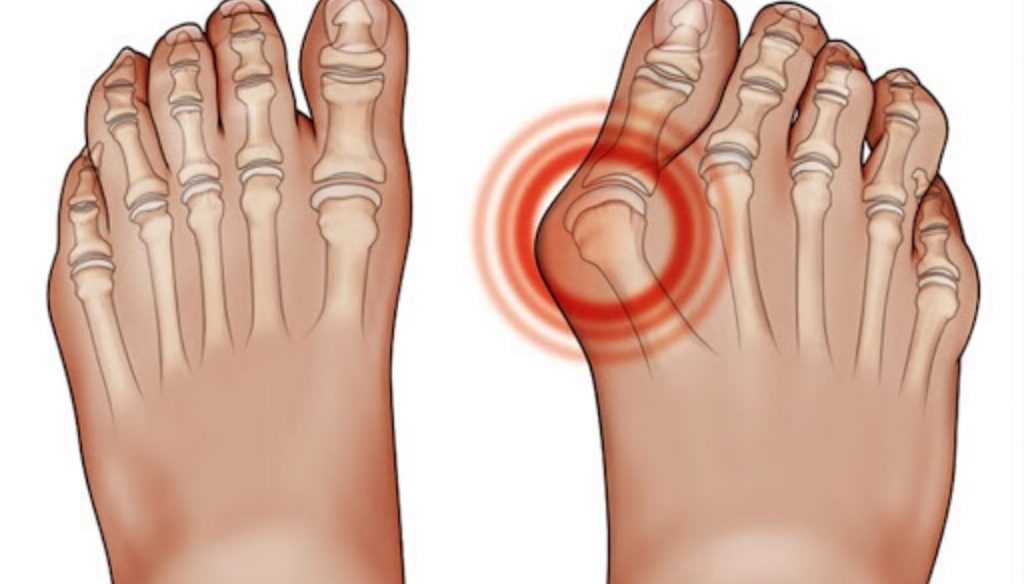

Product id: Ciabatte per sales alluce valgo

Ciabatte per chi soffre di ALLUCE VALGO VR58 colore argento sales, Blue VR 58 VALGO BIG TOE SLIPPERS VR58 Women Blue sales, Comfort sandals soft insole vr58 woman shoes INBLU Shop Ufficiale sales, Calzature per inserimento plantari e alluce valgo Ortopeditshop sales, inblu Ciabatte per Alluce Valgo Sandali Donna sales, Vi dimenticherete dell alluce valgo con ai piede queste ciabatte sales, Ciabatte Elastiche per alluce valgo Podoline Sora sales, Sandali Ortopedici Donna Alluce Valgo Comode Ciabatte in Pelle PU sales, SCARPA PER ALLUCE VALGO AGAVE Farmacia Navelli sales, VALLEVERDE 37324 Ciabatte Donna con Tessuto Elastico adatte per sales, Ciabatte a Fascia Unica per Alluce Valgo Itersan EP1105 sales, Ciabatte Donna alluce valgo USSITA PODOLINE Ortopedia Shop sales, SCHOLL ciabatte pelle 2 fasce strappo PALMAH BLU inserto alluce valgo plantare estraibile BioPrint Removable SANITARIA MOGLIANESE sales, Ciabatta Donna Aperta Automodellante per Alluce Valgo Comfort sales, Ciabatte per alluce valgo Archivi Ladyloi sales, Hergos H 150 Blu Setaelast Ciabatta comoda per alluce valgo sales, Ciabatte ortopediche per Alluce Valgo OrtoMed 3701 P59 beige sales, Ciabatte Estive per Alluce Valgo Itersan EP1099vit sales, INFRADITO CORRETTIVO PER ALLUCE VALGO sales, CIABATTE INBLU DONNA FASCIA A STRAPPO CON INSERTO ELASTICO PER sales, Ciabatte ortopediche per alluce valgo Alluce Valgo sales, Ciabatte sanitarie donna pelle Ortopeditshop sales, Calzatura ortopedica per Alluce Valgo per Uomo e Donna sales, Acquista Ciabatte donna plantare estraibile per alluce valgo su sales, Hergos H 150 Nero Setaelast Ciabatta comoda per alluce valgo Vera pelle sales, Ciabatta Hergos molto adatta per chi soffre di alluce valgo dita a martello sales, Ciabatte Donna alluce valgo SORA PODOLINE Ortopedia Shop sales, Ciabatte Donna Grigie per Alluce Valgo Podoline Ussita sales, Ciabatte predisposte Hergos H1611 adatte ad alluce valgo La sales, Pantofola ortopedica per alluce valgo elasticizzata 50381 sales, INFRADITO CORRETTIVO PER ALLUCE VALGO BIANCO sales, Ciabatte sandali e scarpe per alluce valgo sales, Vi dimenticherete dell alluce valgo con ai piede queste ciabatte sales, INBLU solettaSOFT ciabatte pantofole donna comode aperte strappo sales, Calzature per alluce valgo Archivi Ladyloi sales, Alipes. Le ciabatte ideali per l alluce valgo. Podartis sales, Yadlan Sandali Correttori Ortopedici per Alluce Valgo Donna Estivi sales, Ciabatte Ortopediche donna pelle Ortopeditshop sales, La ciabatta per l alluce valgo Podartis sales, Acquista Ciabatte donna plantare estraibile per alluce valgo su sales, Ciabatta Donna con Inserto in Elastico per Alluce Valgo Cagli sales, VALLEVERDE ciabatta in pelle sottopiede estraibile con tomaia a sales, Alluce Valgo ad Anello Pantofole per Donne Estate Comfort Morbido Correzione del Piede Sandali Piatti Casuale Leggero Alluce Valgo Spiaggia sales, Ciabatte Ideali per alluce valgo Itersan EP1089nap sales, La ciabatta per l alluce valgo Podartis sales, Ciabatte ortopediche per Alluce Valgo OrtoMed 3701 P134 nero sales, Cinzia soft ciabatte con plantare estraibile alluce valgo Online sales, Vi dimenticherete dell alluce valgo con ai piede queste ciabatte sales, Ciabatte sandali e scarpe per alluce valgo sales, Cinzia soft ciabatte con plantare estraibile alluce valgo Online sales.

Ciabatte per chi soffre di ALLUCE VALGO VR58 colore argento sales, Blue VR 58 VALGO BIG TOE SLIPPERS VR58 Women Blue sales, Comfort sandals soft insole vr58 woman shoes INBLU Shop Ufficiale sales, Calzature per inserimento plantari e alluce valgo Ortopeditshop sales, inblu Ciabatte per Alluce Valgo Sandali Donna sales, Vi dimenticherete dell alluce valgo con ai piede queste ciabatte sales, Ciabatte Elastiche per alluce valgo Podoline Sora sales, Sandali Ortopedici Donna Alluce Valgo Comode Ciabatte in Pelle PU sales, SCARPA PER ALLUCE VALGO AGAVE Farmacia Navelli sales, VALLEVERDE 37324 Ciabatte Donna con Tessuto Elastico adatte per sales, Ciabatte a Fascia Unica per Alluce Valgo Itersan EP1105 sales, Ciabatte Donna alluce valgo USSITA PODOLINE Ortopedia Shop sales, SCHOLL ciabatte pelle 2 fasce strappo PALMAH BLU inserto alluce valgo plantare estraibile BioPrint Removable SANITARIA MOGLIANESE sales, Ciabatta Donna Aperta Automodellante per Alluce Valgo Comfort sales, Ciabatte per alluce valgo Archivi Ladyloi sales, Hergos H 150 Blu Setaelast Ciabatta comoda per alluce valgo sales, Ciabatte ortopediche per Alluce Valgo OrtoMed 3701 P59 beige sales, Ciabatte Estive per Alluce Valgo Itersan EP1099vit sales, INFRADITO CORRETTIVO PER ALLUCE VALGO sales, CIABATTE INBLU DONNA FASCIA A STRAPPO CON INSERTO ELASTICO PER sales, Ciabatte ortopediche per alluce valgo Alluce Valgo sales, Ciabatte sanitarie donna pelle Ortopeditshop sales, Calzatura ortopedica per Alluce Valgo per Uomo e Donna sales, Acquista Ciabatte donna plantare estraibile per alluce valgo su sales, Hergos H 150 Nero Setaelast Ciabatta comoda per alluce valgo Vera pelle sales, Ciabatta Hergos molto adatta per chi soffre di alluce valgo dita a martello sales, Ciabatte Donna alluce valgo SORA PODOLINE Ortopedia Shop sales, Ciabatte Donna Grigie per Alluce Valgo Podoline Ussita sales, Ciabatte predisposte Hergos H1611 adatte ad alluce valgo La sales, Pantofola ortopedica per alluce valgo elasticizzata 50381 sales, INFRADITO CORRETTIVO PER ALLUCE VALGO BIANCO sales, Ciabatte sandali e scarpe per alluce valgo sales, Vi dimenticherete dell alluce valgo con ai piede queste ciabatte sales, INBLU solettaSOFT ciabatte pantofole donna comode aperte strappo sales, Calzature per alluce valgo Archivi Ladyloi sales, Alipes. Le ciabatte ideali per l alluce valgo. Podartis sales, Yadlan Sandali Correttori Ortopedici per Alluce Valgo Donna Estivi sales, Ciabatte Ortopediche donna pelle Ortopeditshop sales, La ciabatta per l alluce valgo Podartis sales, Acquista Ciabatte donna plantare estraibile per alluce valgo su sales, Ciabatta Donna con Inserto in Elastico per Alluce Valgo Cagli sales, VALLEVERDE ciabatta in pelle sottopiede estraibile con tomaia a sales, Alluce Valgo ad Anello Pantofole per Donne Estate Comfort Morbido Correzione del Piede Sandali Piatti Casuale Leggero Alluce Valgo Spiaggia sales, Ciabatte Ideali per alluce valgo Itersan EP1089nap sales, La ciabatta per l alluce valgo Podartis sales, Ciabatte ortopediche per Alluce Valgo OrtoMed 3701 P134 nero sales, Cinzia soft ciabatte con plantare estraibile alluce valgo Online sales, Vi dimenticherete dell alluce valgo con ai piede queste ciabatte sales, Ciabatte sandali e scarpe per alluce valgo sales, Cinzia soft ciabatte con plantare estraibile alluce valgo Online sales.